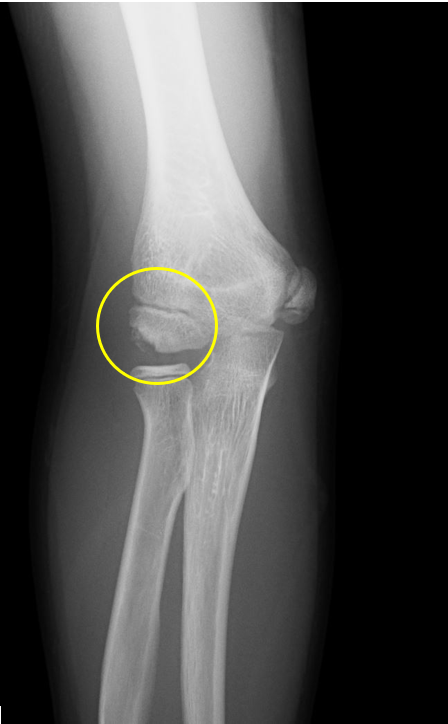

肘離断性骨軟骨炎(野球肘外側型)

肘の離断性骨軟骨炎(以下:OCD:osteochondritis dissecans)は上腕骨小頭という部位に好発することが多いです。

OCDは成長期の代表的なスポーツ障害であり、野球などといった投球・投擲動作を行うスポーツ選手で投球側に発生することが多いです。大半は10-12歳で発症し成長期における有病率は2-3%と頻度は少ないが進行するとスポーツにみならず、日常生活お支障をきたすことが多い怪我です。そのため、早期発見・早期治療が重要となります。

一般的にレントゲンによる分類が用いられ、初期・進行期・終末期に分けられます。

OCDを発見するにはレントゲンや超音波検査で上腕骨小頭軟骨下骨の状態を観察します。

2024年5月、当院受診。レントゲン撮影をして離断性骨軟骨炎と診断されてリハビリ開始。